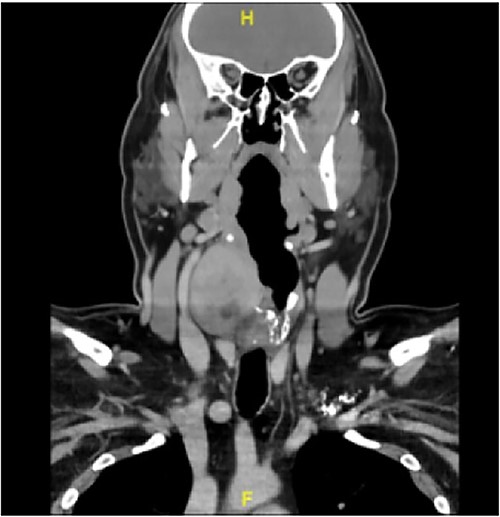

A 40-year-old male with a hypopharyngeal mass was referred to a tertiary head and neck surgical oncology practice after a computerized tomography (CT) scan showed a large 6.5 cm heterogeneously enhancing mass involving the right larynx and hypopharynx, as well as the right thyroid cartilage with local mass effect without separate regional adenopathy (Fig. 1).

CT scan illustrating the large 6.5 cm mass involving the right larynx and hypopharynx.